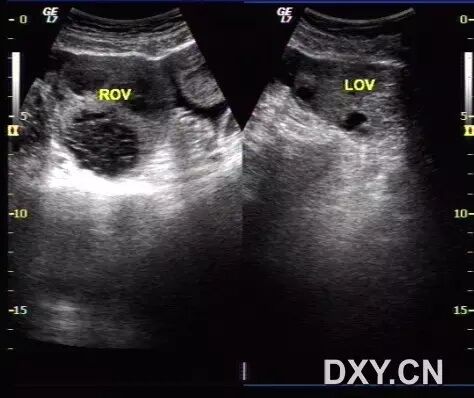

病例3(由丁香园注册用户「香水湾的传奇」提供):女性,26岁,因月经不调服用激素类药物治疗,现下腹痛来诊。

超声发现如下改变:

图1 显示肝脏周边的腹腔积液

图2 显示子宫内膜增厚且回声增强,呈分泌期改变

图3 显示双侧卵巢增大,其内可见多条分隔光带

图4 显示分隔内的丰富血流信号

图5 为治疗后超声改变,可见双侧卵巢体积缩小,卵泡数目减少,盆腔积液消失